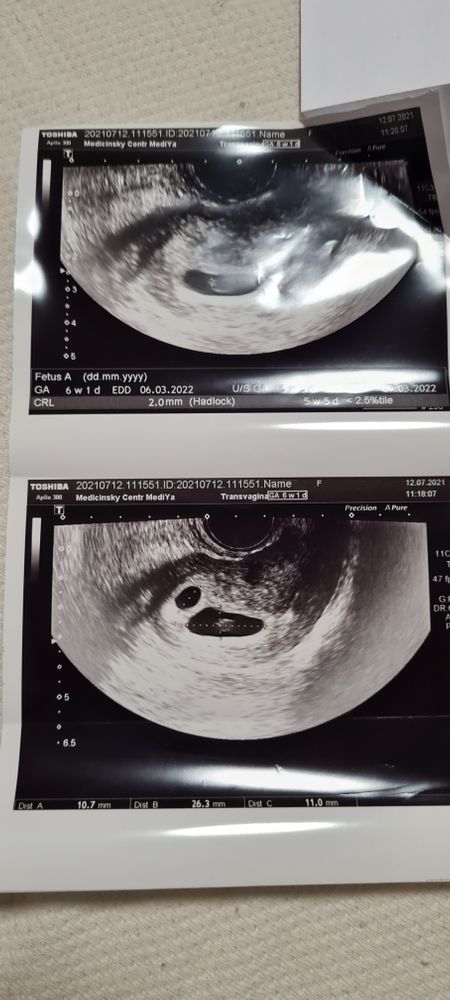

Первое УЗИ на 26 дпп.

Сохранение ЭКО-беременностиПривет, девчонки! Я что то в панике, сходила на УЗИ на 26 дпп, и результаты 2 ПЯ

1- 11*10*11 без эмбриона и без жм,

2-26*11*25, эмбрион нечетко КТР 2,0мм на 5,5нед. жм-3,0мм, сердцебиение четко не определяется.

Заключение УЗИ, что признаки неразвивающейся двойни.